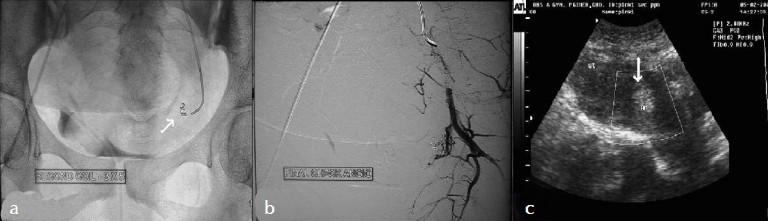

Uterine artery pseudoaneurysm is a rare cause of secondary postpartum hemorrhage but is potentially life-threatening and can occur after caesarean section (c-section) or a hysterectomy. A 28-year-old woman who developed secondary postpartum hemorrhage after c-section was diagnosed to have pseudoaneurysm from the left uterine artery on ultrasound (US) and computed tomography (CT) scan. She was treated with coiling of the pseudoaneurysm with stainless steel coil via selective catheterization of the uterine artery. The procedure was uneventful and the pseudoaneurysm was successfully obliterated. Angiographic embolization is a safe and effective method for treating postpartum hemorrhage due to pseudoaneurysm in hemodynamically stable patients. Therefore, it should be considered as a treatment option before resorting to surgery, in appropriately selected cases.

子宫动脉假性动脉瘤是继发性产后出血的罕见原因,但有潜在生命危险,可发生于剖宫产或子宫切除术后。一名28岁女性在剖宫产后发生继发性产后出血,经超声(US)和计算机断层扫描(CT)诊断为左子宫动脉假性动脉瘤。通过子宫动脉选择性插管,用不锈钢线圈对假性动脉瘤进行了栓塞治疗。手术过程顺利,假性动脉瘤成功闭塞。对于血流动力学稳定的患者,血管造影栓塞术是治疗假性动脉瘤所致产后出血的一种安全有效的方法。因此,在适当选择的病例中,在采取手术治疗之前应考虑将其作为一种治疗选择。